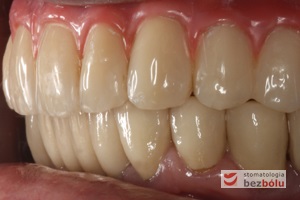

Ostateczny efekt estetyczny wieńczący proces terapeutyczny - odbudowa protetyczna obu łuków zębowych przy zastosowaniu implantów Friadent Ankylos

Ostateczny efekt estetyczny wieńczący proces terapeutyczny – odbudowa protetyczna obu łuków zębowych przy zastosowaniu implantów Friadent Ankylos